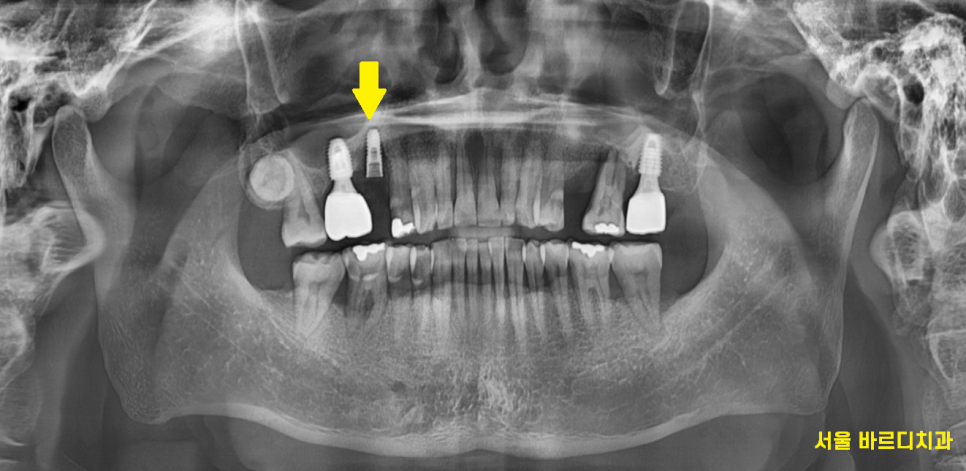

230427

왼쪽 위에 먼저 임플란트 1개를 식립하였습니다.

한쪽씩 치료를 원하셨던 환자분이라

왼쪽 치료가 끝나면

오른쪽 치료를 해드리기로 했는데요.